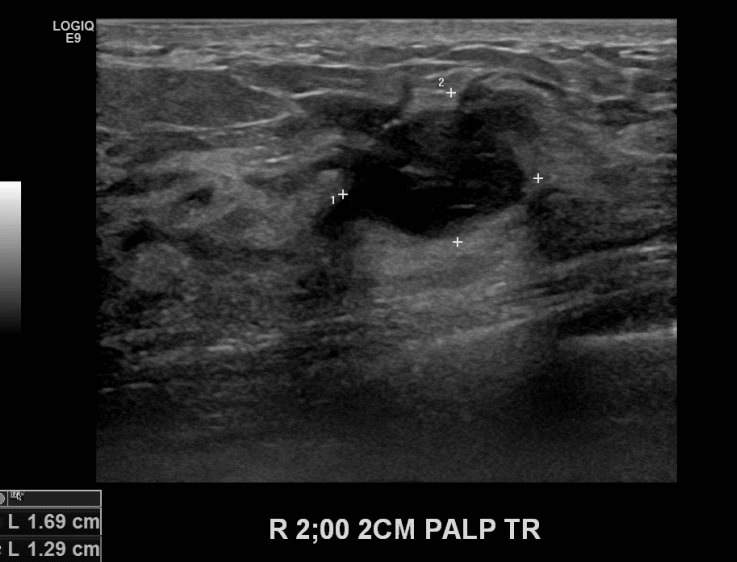

상기환자 우측유방의 만져지는 멍울있어 내원하신 50대 여성으로 유방초음파검사 이후

의심스러운 혹 조직검사시행후 유방암 진단되었습니다